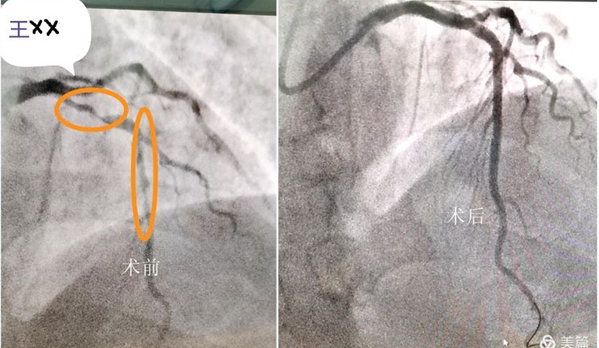

案例一:冠状动脉造影+支架植入术(PCI)

经主治医生和科主任刘智林、高伟的综合评估,治疗团队一致认为需要用冠状动脉造影术为患者进行下一步的检查治疗。经过充分的术前准备,心血管内科介入中心团队在高伟副主任医师的指导下,在介入中心王永杰、郝李园两位医师的协调下,为患者在介入导管室内成功实施冠状动脉造影术+支架植入术,检查结果显示前降支近端60%-90%狭窄,中段80%狭窄,经过与患者家属的充分沟通,并征得其同意后,按照相关诊疗原则,治疗团队随即为患者行冠状动脉支架植入术(PCI),对前降支行PCI术,于前降支中段病变处及左主干处植入支架2枚,多角度造影显示支架植入处血管狭窄消失,血流通畅,无夹层形成,术后患者生命体征平稳,安全返回病房,目前病情稳定,胸闷症状明显改善。